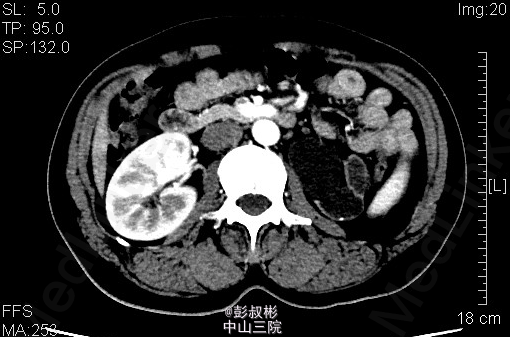

患者女性,47岁,左腹部胀痛1月余。既往有“双肾结石”病史10余年。其余见双肾CTU。根据检查判断肾的病变?